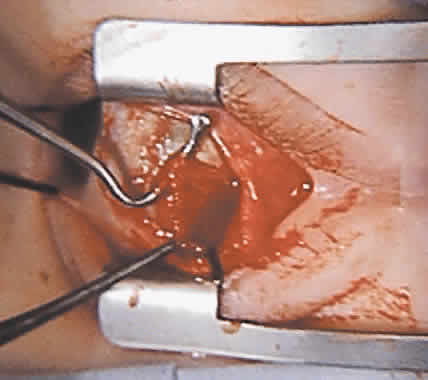

To perform the procedure, either general anesthesia or local anesthesia with intravenous sedation may be selected. Following anesthesia, it is often helpful to assess tendon laxity by performing an exaggerated traction test.47 A normal superior oblique tendon can be differentiated from a lax tendon when the globe is rotated upward, inward, and retropulsed into the orbit (Fig. 3).23

The superior oblique tendon tuck is best performed near the tendon's insertion as described by McLean.48 The surgical procedure is performed through a superior temporal cul-de-sac approach (Fig. 4). With the globe depressed, an incision is made through the conjunctiva and Tenon's fascia just temporal to the lateral border of the superior rectus muscle and parallel to the corneoscleral limbus. The superior rectus muscle is engaged on a muscle hook and the globe adducted and positioned in maximal depression. The lateral rectus muscle may also be used to assist positioning the globe. Using two small muscle hooks, the conjunctival incision is stretched open posteriorly in a triangular fashion. The lateral border of the superior rectus muscle is elevated and displaced medially. The globe is then examined for the glistening, white fibers of the superior oblique tendon running flush against the sclera and directed anteromedially. The anterior portion of the reflected tendon typically inserts under the lateral border of the superior rectus muscle, 5 to 7 mm posterior to its insertion. However, this location may vary, and anatomic anomalies are common (Fig. 5).12,37,47,48 The superior oblique tendon looks very different near its scleral insertion than 10 mm more proximally, where it becomes cordlike and enters Tenon's fascia after passing under the belly of the superior rectus muscle. Inexperienced surgeons have mistaken the lateral portion of the tendinous insertion of the superior rectus muscle for the superior oblique tendon (Fig. 6).49 However, the superior rectus muscle travels toward the orbital apex and contains prominent anterior ciliary blood vessels, whereas the superior oblique tendon is directed toward the trochlea and is usually avascular. In addition, direct traction on the superior oblique tendon can easily be palpated at the trochlea by pressing a finger over the eyelid in the superior nasal quadrant of the orbit.10 This is a reliable sign that the tendon (and not some other structure) has been engaged on the muscle hook.